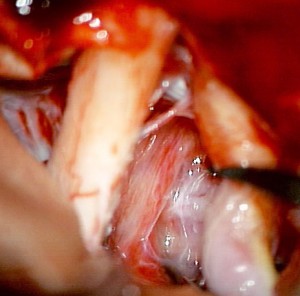

右の視神経管を開けて視神経を可動化して,視神経と内頚動脈の間から観察しています。のう胞性頭蓋咽頭腫 cystic craniopharyngioma ののう胞を破って内用液を排出した段階の写真です。腫瘍を摘出し始めた時には全く見えなかった rete mirabilisが顕在化してきます。なんとなく正常の下垂体柄に似ていますが門脈血管の本数が少ないです。ポイントは,細い血管が同じ方向に流れるように走るところです。rete mirabilisを見つけて残せれば,下垂体柄の機能を温存することができます。ですから,鞍上部の頭蓋咽頭腫をいじるときには,同じ方向に流れる細い血管 rete mirabilis に注意を払うことが大切です。